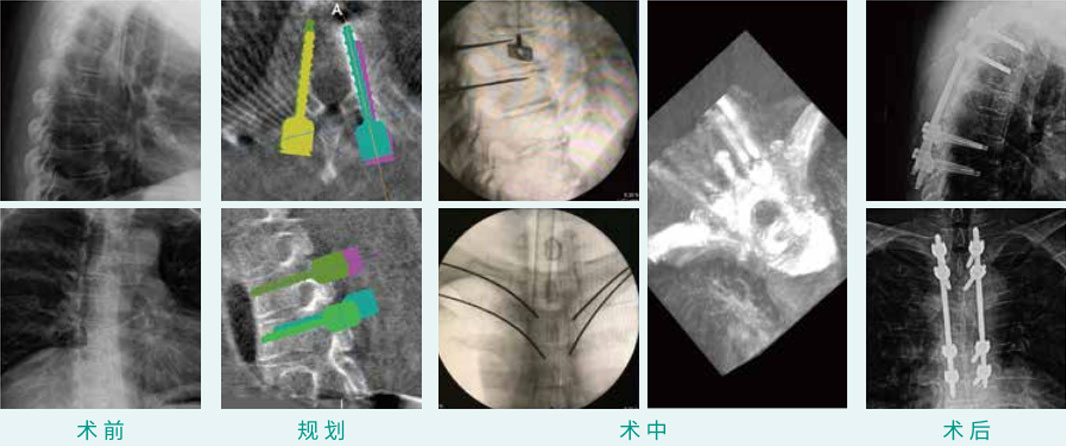

椎弓根钉经皮内牢靠术

天玑? 辅助T2, T3, T6, T7椎弓根钉经皮内牢靠术

基本情形:患者男,55岁

机械人累积用时:20分钟

植入物:8枚经皮椎弓根螺钉

病例泉源:中国医科大学隶属第一医院 朱悦 丛琳